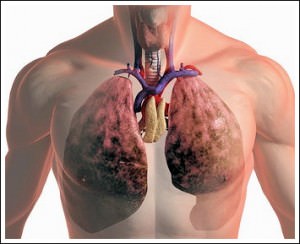

На первом месте по структуре заболеваемости и смертности стоят злокачественные опухоли, вызванные или

Основной причиной снижения смертности от рака легких в мире стало введение жестких антитабачных законов и мероприятий. У нас же в стране снижение этого показателя произошло за счет взятия под контроль химического состава табачного дыма, — утверждает профессор. Чуть более 10 лет назад был принят специальный регламент, устанавливающий допустимый уровень смол в табачном дыме, что, как мы видим, привело к положительной динамике.